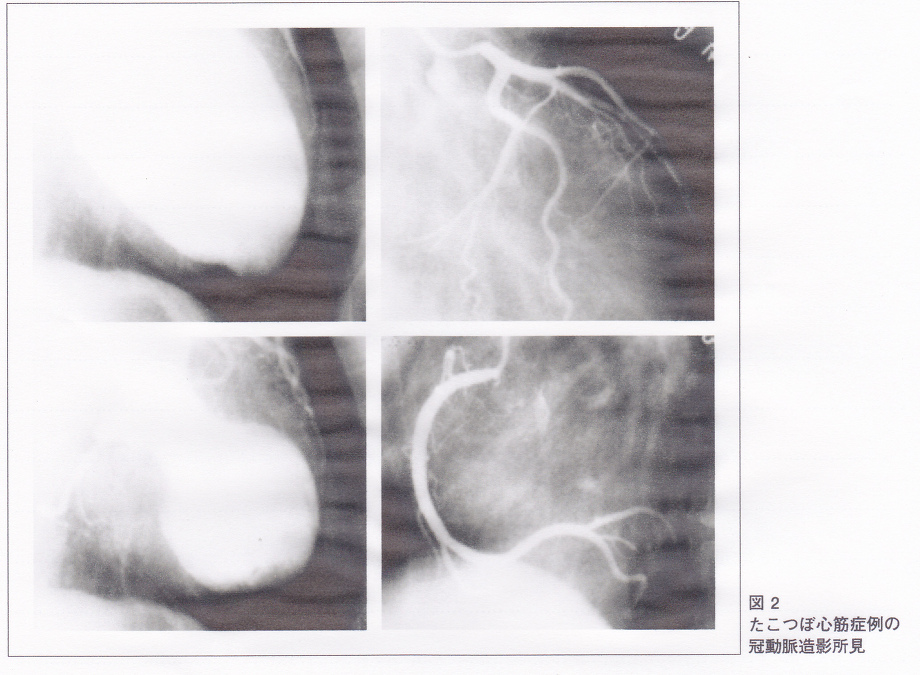

急性前壁心筋梗塞(antAMI)の波形と紛らわしいものの一つとしてタコツボ心筋症(TC)がある。

上図のように、冠動脈に病変がなく、左室の壁運動として心尖部の心筋がほとんど動かず、心基部のみが収縮するので、左室造影で蛸壺のように見えるものである。

TC 23例とantAMI 342例を比較したところ、TC例では高齢(70 vs 61歳)であり、女性が高率で(85 vs 15%)、心電図では異常Q波を認めない例(42 vs 26%)、対側性変化である下壁誘導のST低下を認めない例(94 vs 51%)が高率で、最大QTc間隔は延長し(567 vs 489mV)、最大ST上昇は軽度(5 vs 3mm)、ST上昇(肢誘導は>0.5mm、前胸部誘導は>1.0mm)を認める誘導数が多かった(8 vs 6)。その上、ST上昇の誘導が異なり、TCでは-aVR誘導のST上昇(=aVR誘導のST低下)が最も高率でV1誘導のST上昇が最も低率であった。aVR誘導のST低下を認め、V1誘導でST上昇を認めない場合はTCと診断すると、感度は91%、特異度は96%であり、心電図指標の中で最も良好だった。